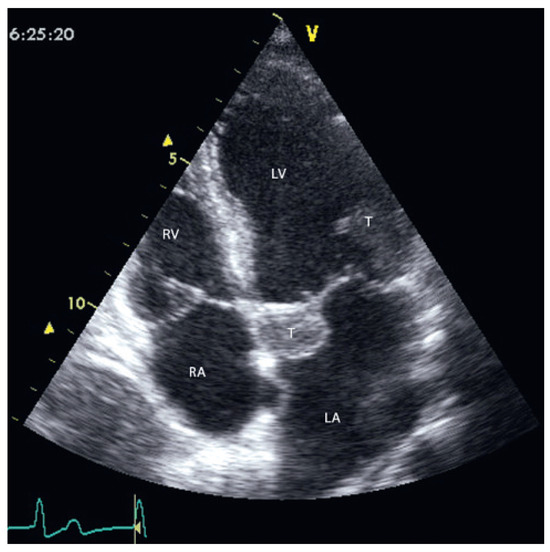

Up to ten percent of acute coronary syndromes occur during or shortly after physical exercise. In fact, physical exertion of more than 4 METs transiently increases the risk for myocardial infarction which remains elevated until an hour afterwards. Th...